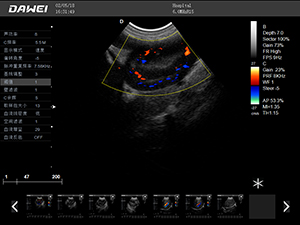

F5-VET彩色多普勒動物超聲診斷儀

F5-VET是一款性能可靠的獸用全數字彩色多普勒超聲診斷系統,基于Windows平臺 配置固態盤快速啟動 穩定可靠,融合了全面豐富的臨床應用,結合優異的人機工程學設計,推動了臨床診斷新趨勢。

·探頭接口:≥4個 可配備凸陣、微凸陣、線陣、相控陣、經直腸等各類獸用專用探頭,并配有犬、貓、馬等動物的專用測量軟件,是一款應用全面的獸用彩超。

·中小動物的肝、膽,脾、腎、膀胱、子宮、妊娠等各組織器官的檢查和病變的診斷